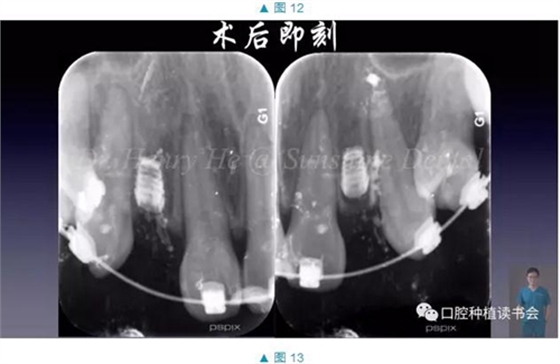

經(jīng)過虛擬種植,我們對鄰牙位置,以及缺牙區(qū)域牙槽骨情況有了深入了解和充分準備,按照這個計劃進行了手術(shù)(圖7-13)

手術(shù)順利,術(shù)后患者未訴疼痛和腫脹。7天拆線,3個月后進行了微創(chuàng)的二期手術(shù),暴露植體,開始進入修復(fù)階段。